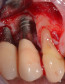

IL TRATTAMENTO DELLE PERI-IMPLANTITI E DELLE RECESSIONI PERI-IMPLANTARI

Nell’ambito della comprovata sopravvivenza a lungo termine degli impianti dentali, la peri-implantite rappresenta una rilevante complicanza – per diffusione e per gravità – che occorre imparare a gestire per non andare incontro a fallimenti. Nello stesso modo la recessione gengivale o la perdita di volume dei tessuti molli in sede peri-implantare possono minare la validità estetica di un trattamento implanto-protesico.

È obiettivo del corso illustrare - e insegnare ad eseguire attraverso esercitazioni pratiche su mascellari animali e su simulatori - strategie e tecniche chirurgiche di pratica applicazione, utili sia per prevenire al massimo l’insorgenza di tali complicanze sia, quando le stesse si siano già manifestate, per risolvere le situazioni di infezione e di perdita dei tessuti di supporto peri-implantari.